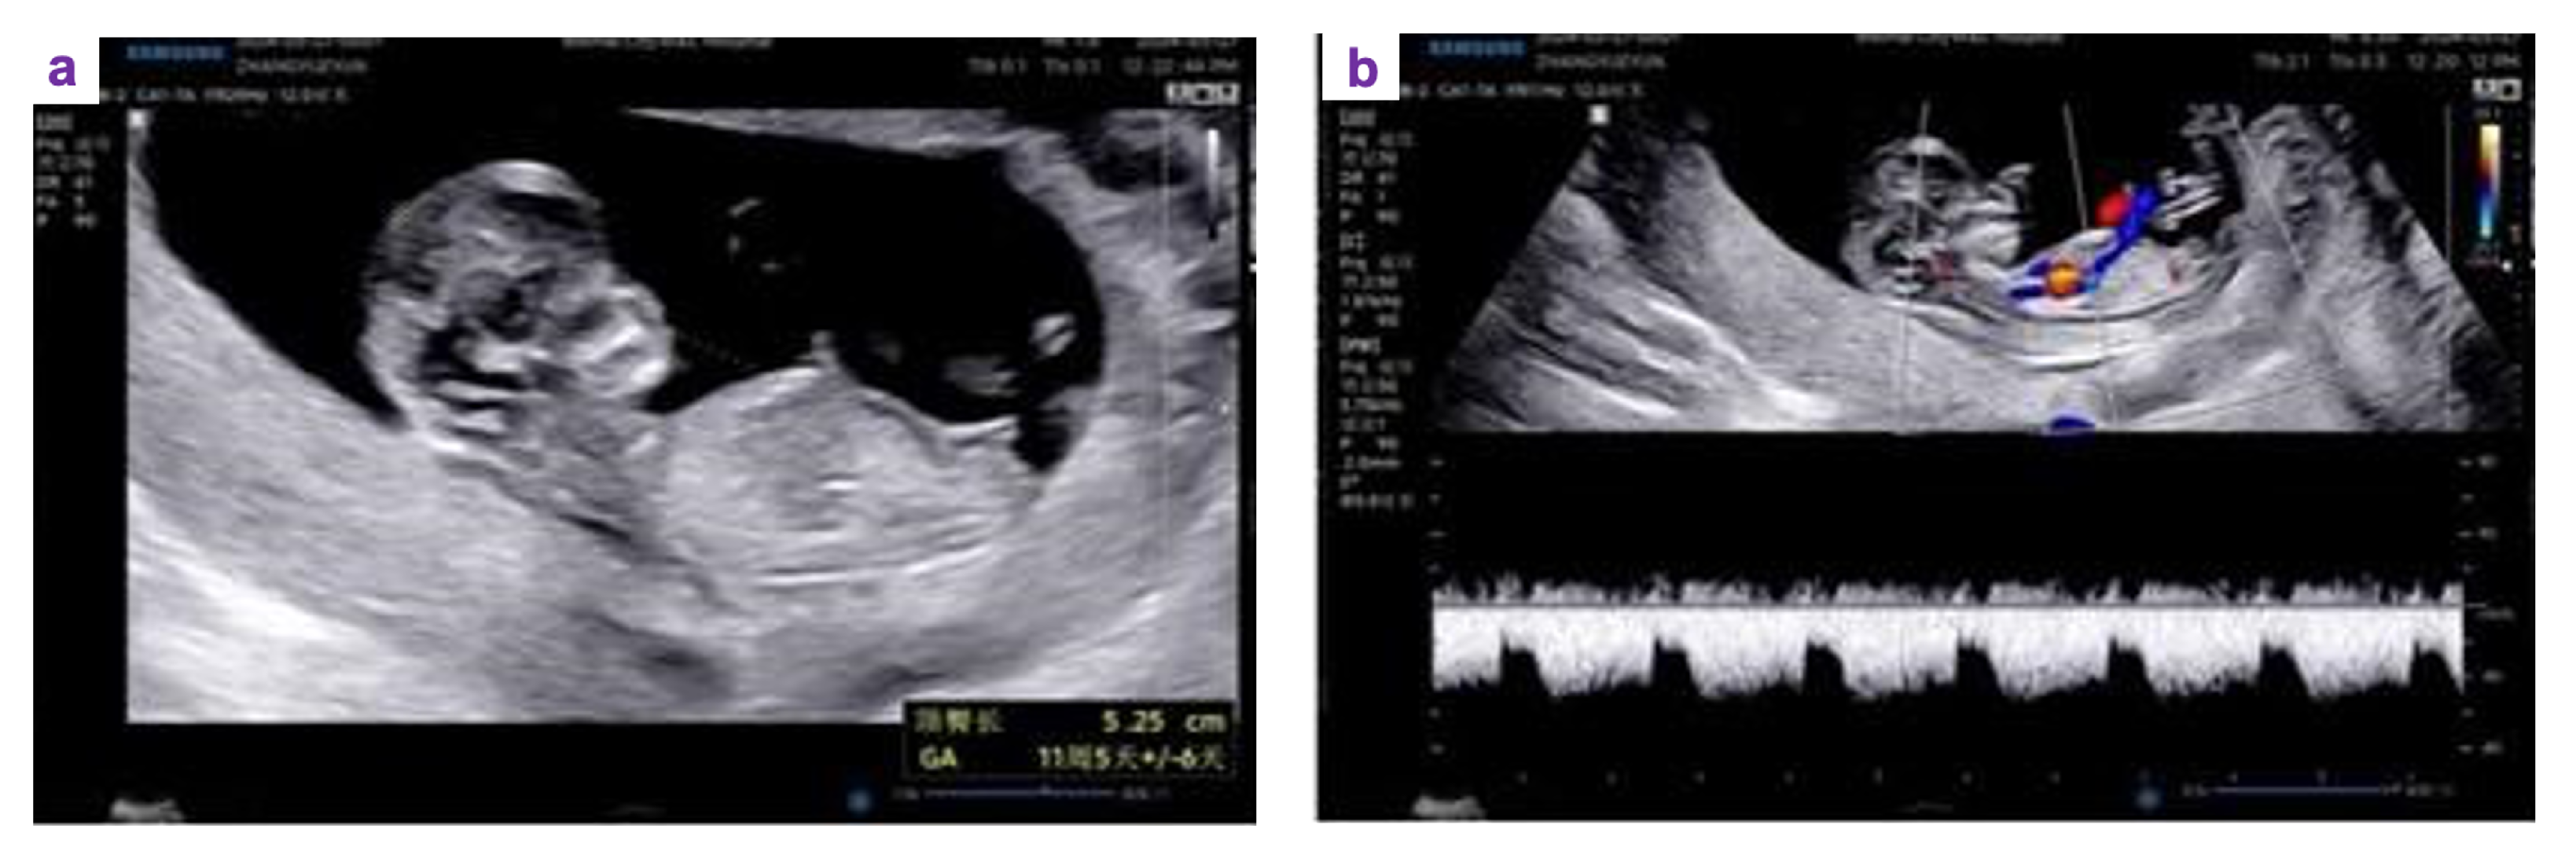

Six courses of paclitaxel (175 mg/m2)/carboplatin (AUC 6) in combination with adjuvant chemotherapy were administered smoothly. To protect ovarian function during chemotherapy, gonadotropin-releasing hormone agonist (GnRH-a, leuprolide depot) was administered every 28 days for a total of six doses. Regular monitoring of clinical presentation was performed every three months after completion of chemotherapy. The tumor markers were all within the normal range. Approximately one year after completing chemotherapy, the patient underwent in vitro fertilization and embryo transfer (IVF-ET). A successful pregnancy was achieved after the second embryo transfer. The ultrasound examination demonstrated a viable intrauterine pregnancy with normal fetal development (Figure 3).

Figure 3. Ultrasound examination confirming successful pregnancy after fertility-sparing surgery. A viable intrauterine pregnancy was observed at 11+4 weeks of gestation, with a crown–rump length of 52 mm and normal fetal cardiac activity. The right ovary showed a cystic lesion measuring approximately 48×31 mm with homogeneous internal echoes.